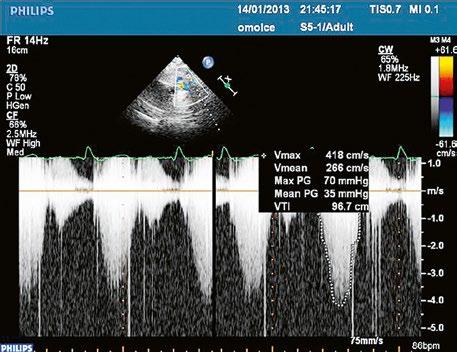

Obr. 45.45 Těžká, dlouhodobě neřešená valvární a subvalvární stenóza plicnice s vysokým gradientem 155/82 mmHg (CW doppler) (viz též Obr. 45.44)